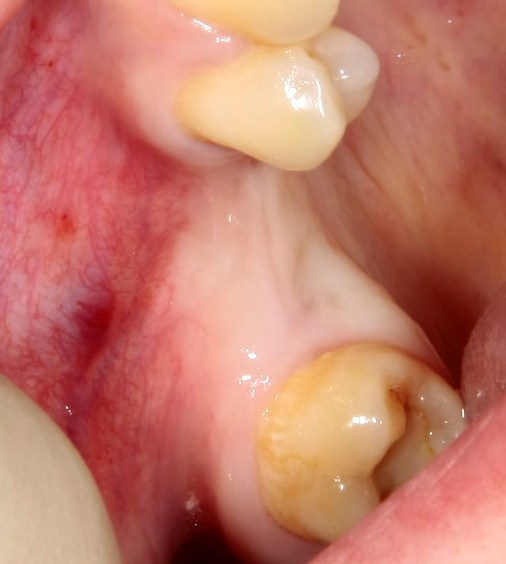

Простой. Надежный. Дешевый. Способ остеопластики.